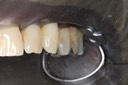

Gary Umeda #12-13 finish –